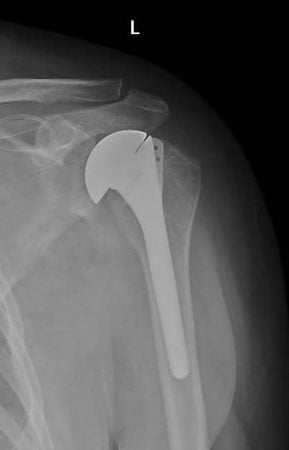

Un tânăr giurgiuvean diagnosticat cu necroză a capului humeral,în luna noiembrie 2023, a primit șansa la o viață normală, după implantarea unei proteze de umăr în cadrul serviciului de ortopedie și traumatologie.

Este de menționat faptul că acest tip de intervenție chirurgicală se face doar într-un număr limitat de unități medicale din Romania.

La doar două luni de la intervenție, tânărul este recuperat în proporție de 80%.